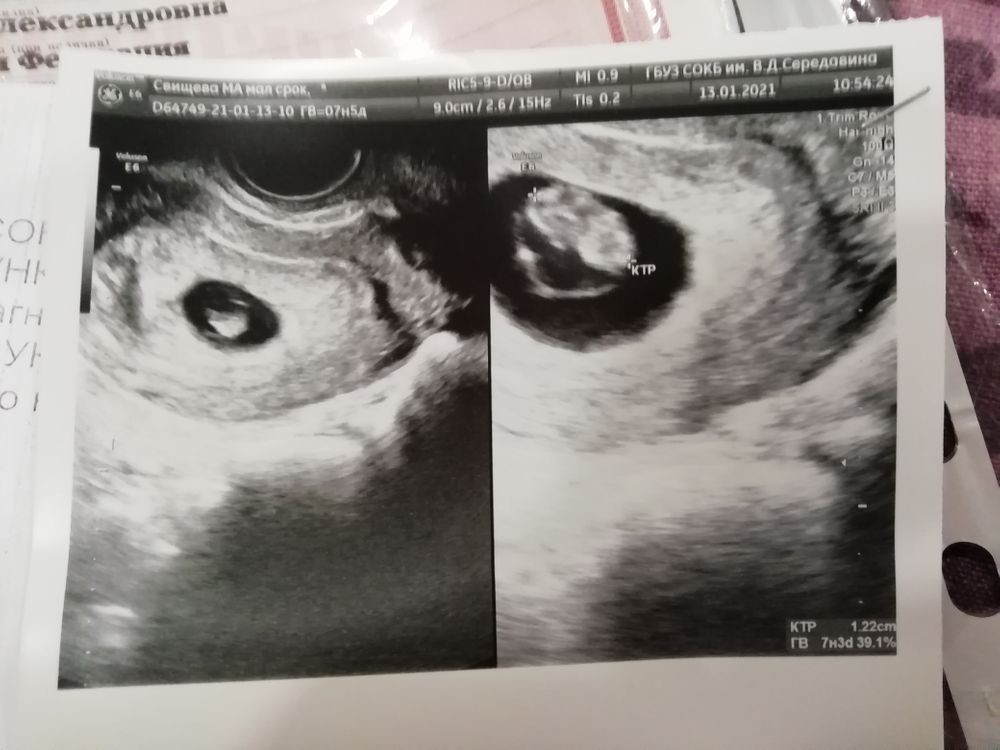

Первое УЗИ. Гематома.

Вот наше первое УЗИ. Услышала сердечко, необычное чувство. Обнаружили гематому, сказали небольшая. Начиталась в интернете про неё, теперь не покидает волнение. На учёт ещё не встала, завтра пойду к гинекологу, пусть говорит, что делать... А пока буду стараться соблюдать полный покой, постельный режим.